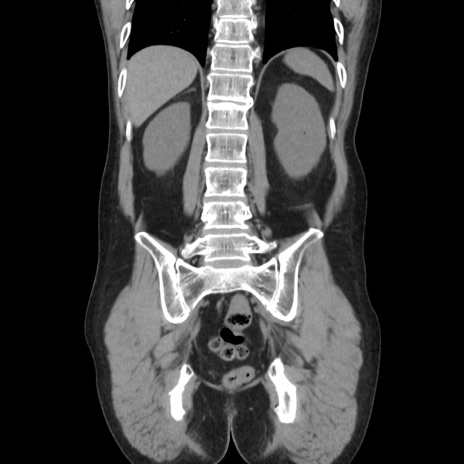

症例37(冠状断像)

【症例】40歳代 男性

【主訴】腹痛

【現病歴】4時間ほど前に電車に乗車中に臍部上より腹痛出現。徐々に増悪し起立困難となり、救急外来受診。生ものは数日食べていない。今朝お雑煮を食べた。

【身体所見】BT 36.8℃、BP 117/84mmHg、HR 91/min、SpO2 97%、苦悶様、腹部:臍上部広範囲圧痛あり、反跳痛±

【データ】WBC 8100、CRP 0.03